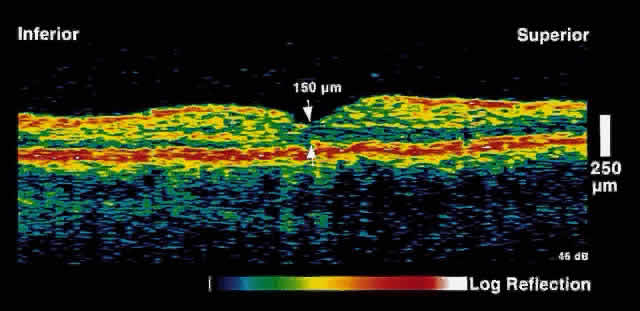

Fig. 3. Several weeks later, an OCT taken through the same area reveals partial

resolution of the neurosensory detachment. Fig. 3. Several weeks later, an OCT taken through the same area reveals partial

resolution of the neurosensory detachment.